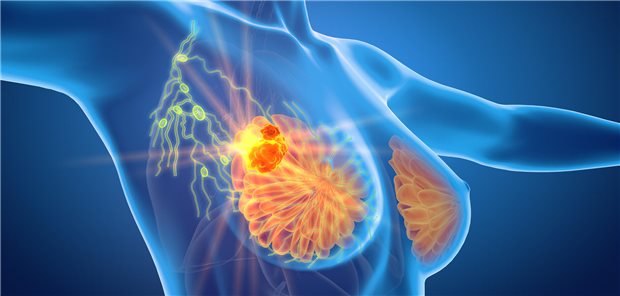

Brustkrebs in der Grundlagenforschung

Zelllinien beim Mamma-Ca charakterisiert